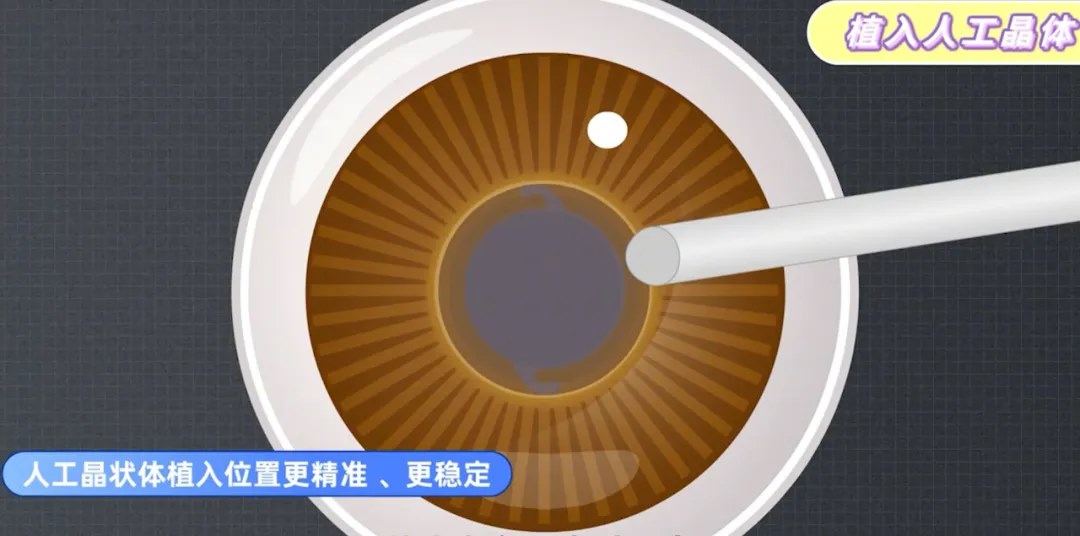

针对硬核,膨胀期,过熟期白内障、先天性白内障、年轻人白内障以及糖尿病白内障患者,相比传统手术,飞秒激光白内障手术更有优势。

传统的白内障手术,在超声乳化的关键步骤制造切口和撕囊时,都是依靠医生手动操作。所以,医生的经验和技巧非常重要,切口会影响恢复速度和术后视力,容易产生机械变形和渗透,而手工撕囊的质量影响术后并发症和视觉质量。

随着技术发展,以飞秒激光辅助白内障手术技术为代表的,前沿手术方式正受到越来越多人的青睐。

飞秒激光可以代替医生的手工切口,预先分割囊膜内的混浊晶体,整个过程都有电脑扫描成像技术辅助,可以准确地制造切口并撕囊,使其光滑平整,还可以利用飞秒激光去除患者部分散光问题,再用超声波去除晶体。